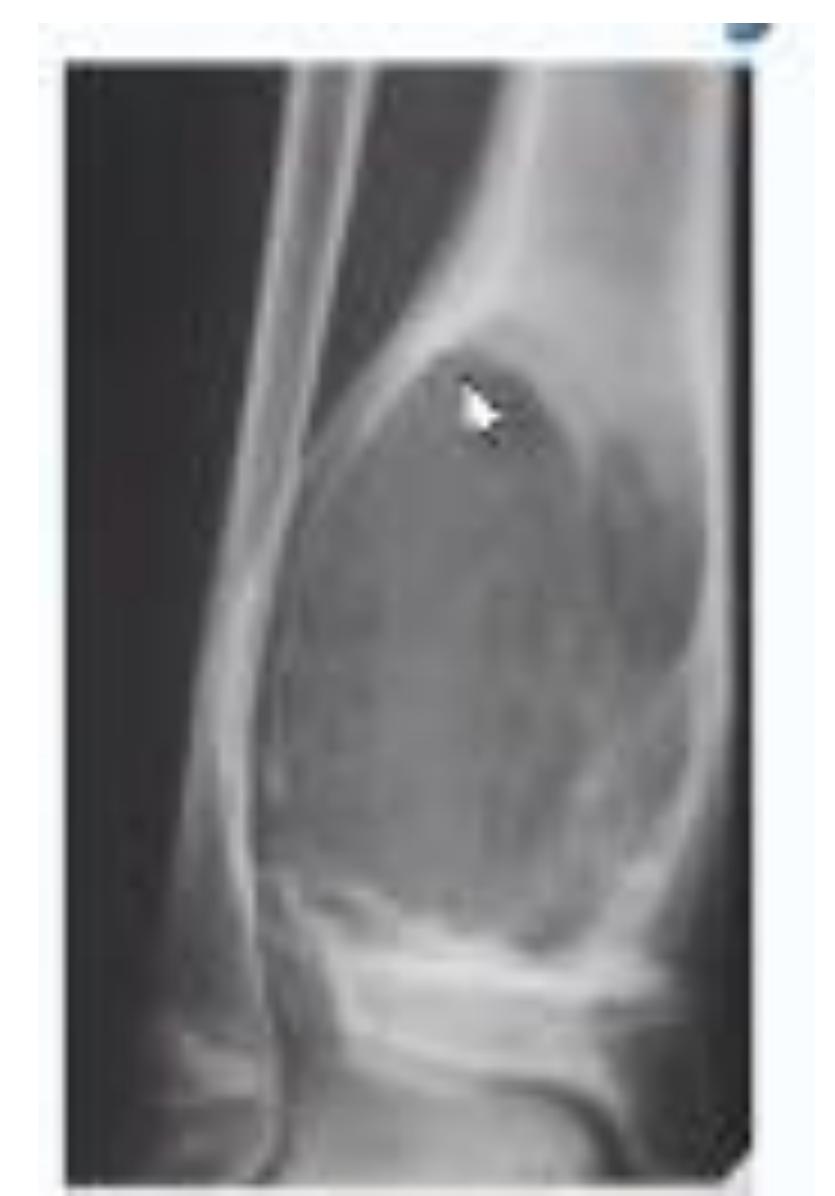

- What is the characteristic finding in supracondylar fractures? Supracondylar fracture in children with fat pad sign

Treatment Protocol

- What are the treatment options for supracondylar fractures?

- If not displaced: Back slab above elbow (flexed elbow)

- If displaced: Closed reduction and fixation with K-wires and slab

Emergency Room Management: Back slab with flexion in 30 degrees and send for AP and L x-rays